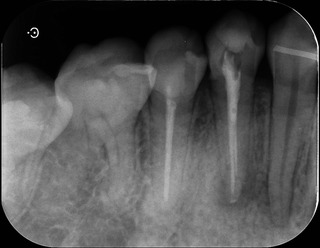

レントゲン。

赤丸の部分が根尖部分の透過像。黒くなっていると思います。

聞くと、10数年前に治療したとのこと。

5番と同じく根尖までキレイに根充材は入っていますが‥

おそらく同じような時期に治療されたのかな?と思います。

通常、根管治療した歯はクラウンにするのが通法ですが。

まだ年齢的に若いし、歯質が残っていたからでしょうね。グッジョブです。